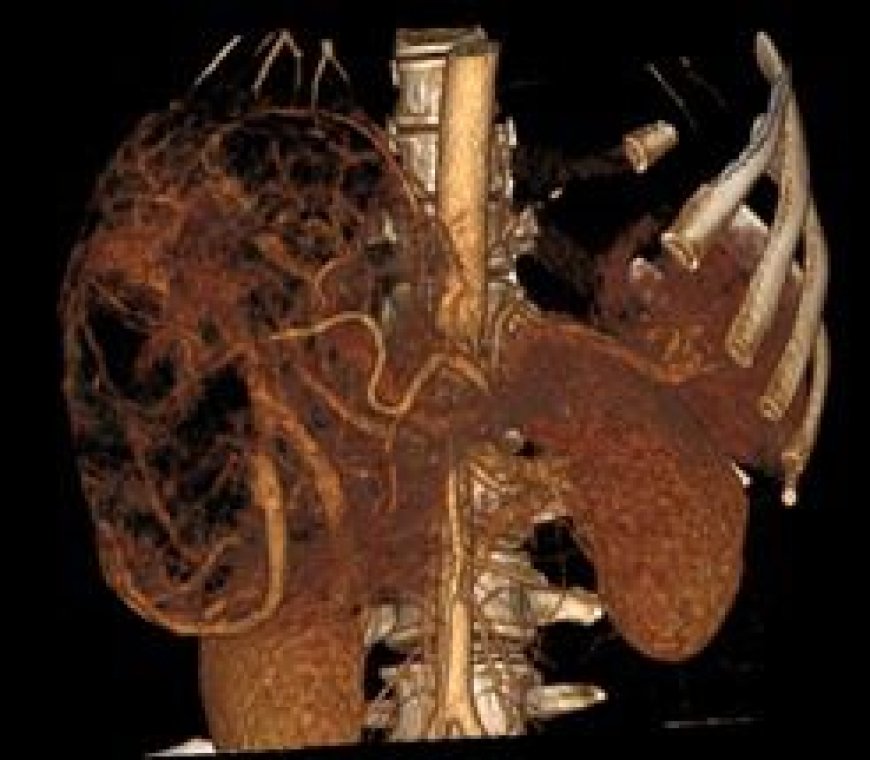

सीटी स्कैन और थ्रेड वेस्कुलर रिकंस्ट्रक्शन से पता चला कि यह ट्यूमर अत्यधिक रक्तसंचारित था और IVC (इंफीरियर वेना केवा), यकृत, दाहिनी वृक्क शिरा, डायाफ्राम और ड्योडेनम जैसे महत्वपूर्ण अंगों के अत्यंत समीप था, जिससे शल्य चिकित्सा अत्यंत जटिल बन गई।